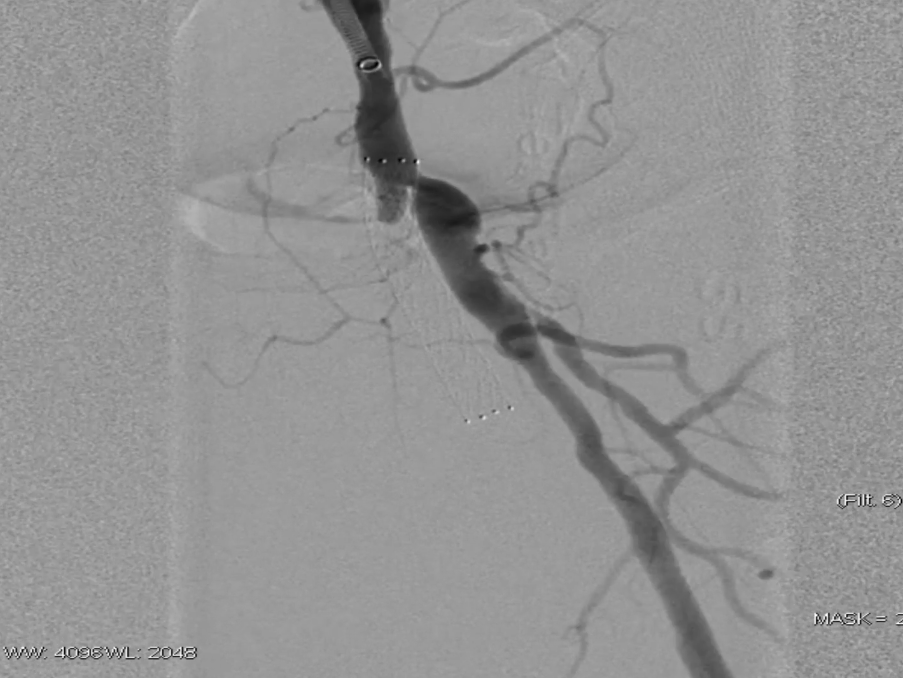

栓塞处理:造影发现管腔获得尚可,但是流速明显较慢,考虑保护伞上方管腔闭塞(考虑斑块/血栓脱落),用6F导管反复抽吸后收回保护伞。

夹层发现及处理:

更换V18导丝后造影显示,胫后动脉血流通畅,胫前动脉疑似仍有小的血栓脱落,导致栓塞。

股浅动脉全程管腔获得尚可,但中段有明显的夹层形成,

先用5mm长球囊充分预扩张;再次造影显示,股浅动脉近中段管腔获得良好,中远段仍有大量的夹层

采用药物涂层球囊(DCB)对股浅动脉病变段全程覆盖:近端用5-250新型药涂球囊,远端用5-150 impact 药涂球囊;

造影显示中段仍有局限性夹层,为保证远期通畅率,植入补救性支架并以5mm球囊后扩张